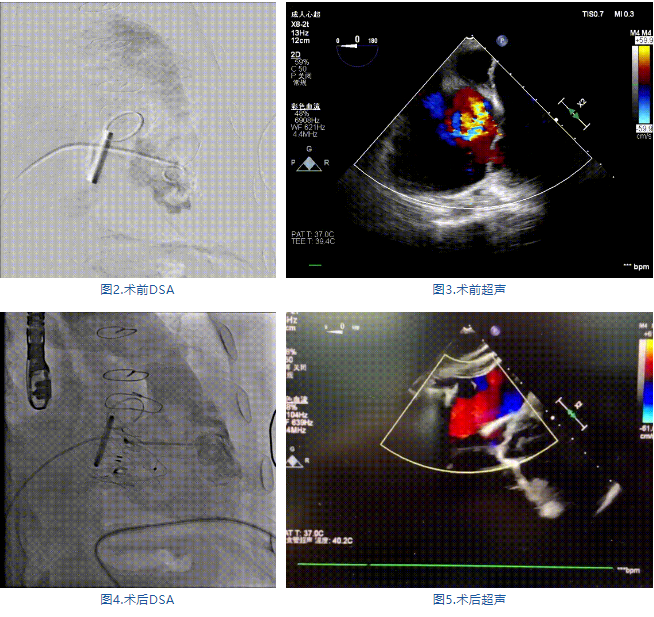

手術(shù)在全麻狀態(tài)下進(jìn)行,郭惠明教授團(tuán)隊(duì)采用經(jīng)右側(cè)頸靜脈入路的方式送入輸送器進(jìn)入體內(nèi),并在TEE和DSA的指引下進(jìn)行。在輸送器進(jìn)入右室后釋放室間隔錨定裝置,旋轉(zhuǎn)輸送器,使得錨定裝置對(duì)準(zhǔn)室間隔面;而后釋放前瓣夾持件,確定夾持件位于右室側(cè)釋放LuX-Valve Plus人工瓣膜盤片,再使用DSA和超聲確認(rèn)盤片是否位于右房側(cè),同時(shí)調(diào)整瓣膜的同軸性。緊接著在DSA和超聲的監(jiān)視下調(diào)整室間隔錨定件貼合室間隔,釋放室間隔錨定裝置。再次確認(rèn)瓣膜的穩(wěn)定性和同軸性后,將輸送器撤出體內(nèi),最終完成LuX-Valve Plus人工瓣膜植入(圖2-5),手術(shù)獲得圓滿成功?;颊咴谑中g(shù)室即刻拔除氣管插管,術(shù)后超聲提示LuX-Valve Plus人工三尖瓣瓣膜同軸性良好,瓣架固定牢靠,無反流和瓣周漏。